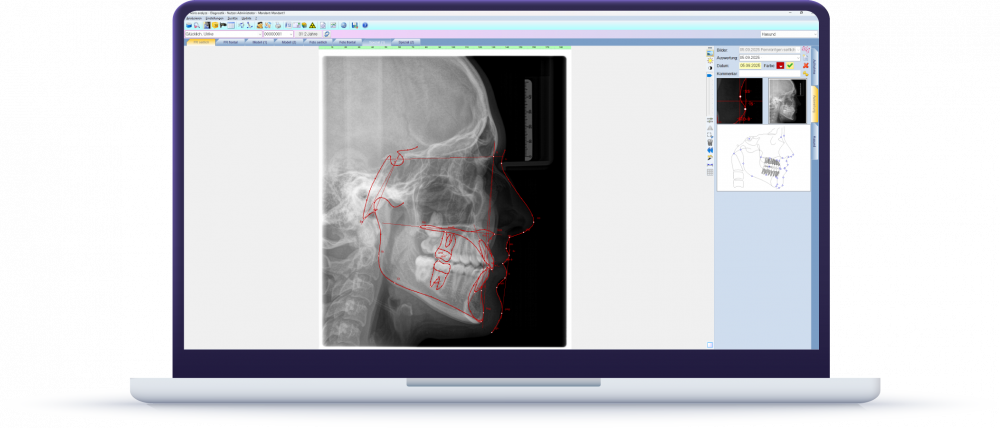

Mehr Klarheit in der Diagnostik mit ivoris® analyze

Ob Röntgen-, Foto- oder 3D-Aufnahmen – die Auswertung erfolgt direkt aus der Patientenakte. Vielfältige Darstellungsmodi erleichtern die Befundung und machen Ihre Ergebnisse auch für Patienten anschaulich. Über 100 Analysevorlagen geben Ihnen die Sicherheit, immer die passende Grundlage für Ihre Behandlungsplanung zu nutzen.